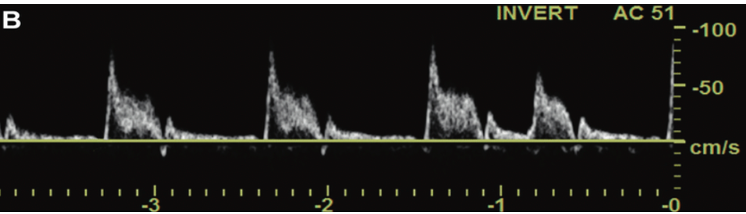

This waveform best matches which artery?

A

ECA